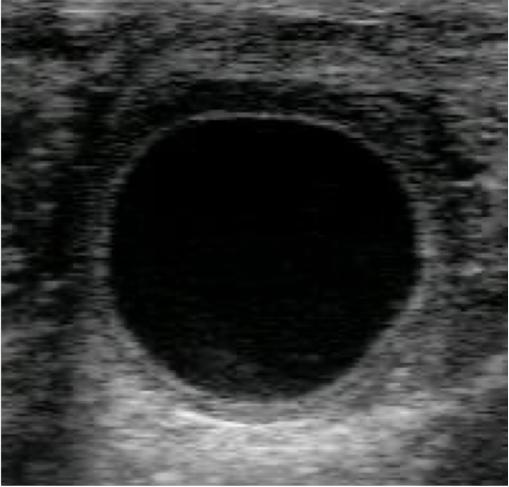

По обычной классификации мы знаем, что есть фолликулярные кисты и лютеиновые кисты (кисты 1 типа и 2 типа).

А что если я скажу, что в последнее время мировое сообщество определило кисты 3го типа? А 95% тел, которые мы диагностируем как лютеиновые кисты, не являются таковыми и в целом не требуют затрат на их лечение и каких-либо манипуляций?

Также большинство учёных предлагают пересмотреть классификацию на просто патологические и не патологические кисты...

Предлагаю рассмотреть снимки и в комментариях ответить, какие кисты вы видите и кисты ли это, а потом будем разбираться с каждым случаем в отдельности!